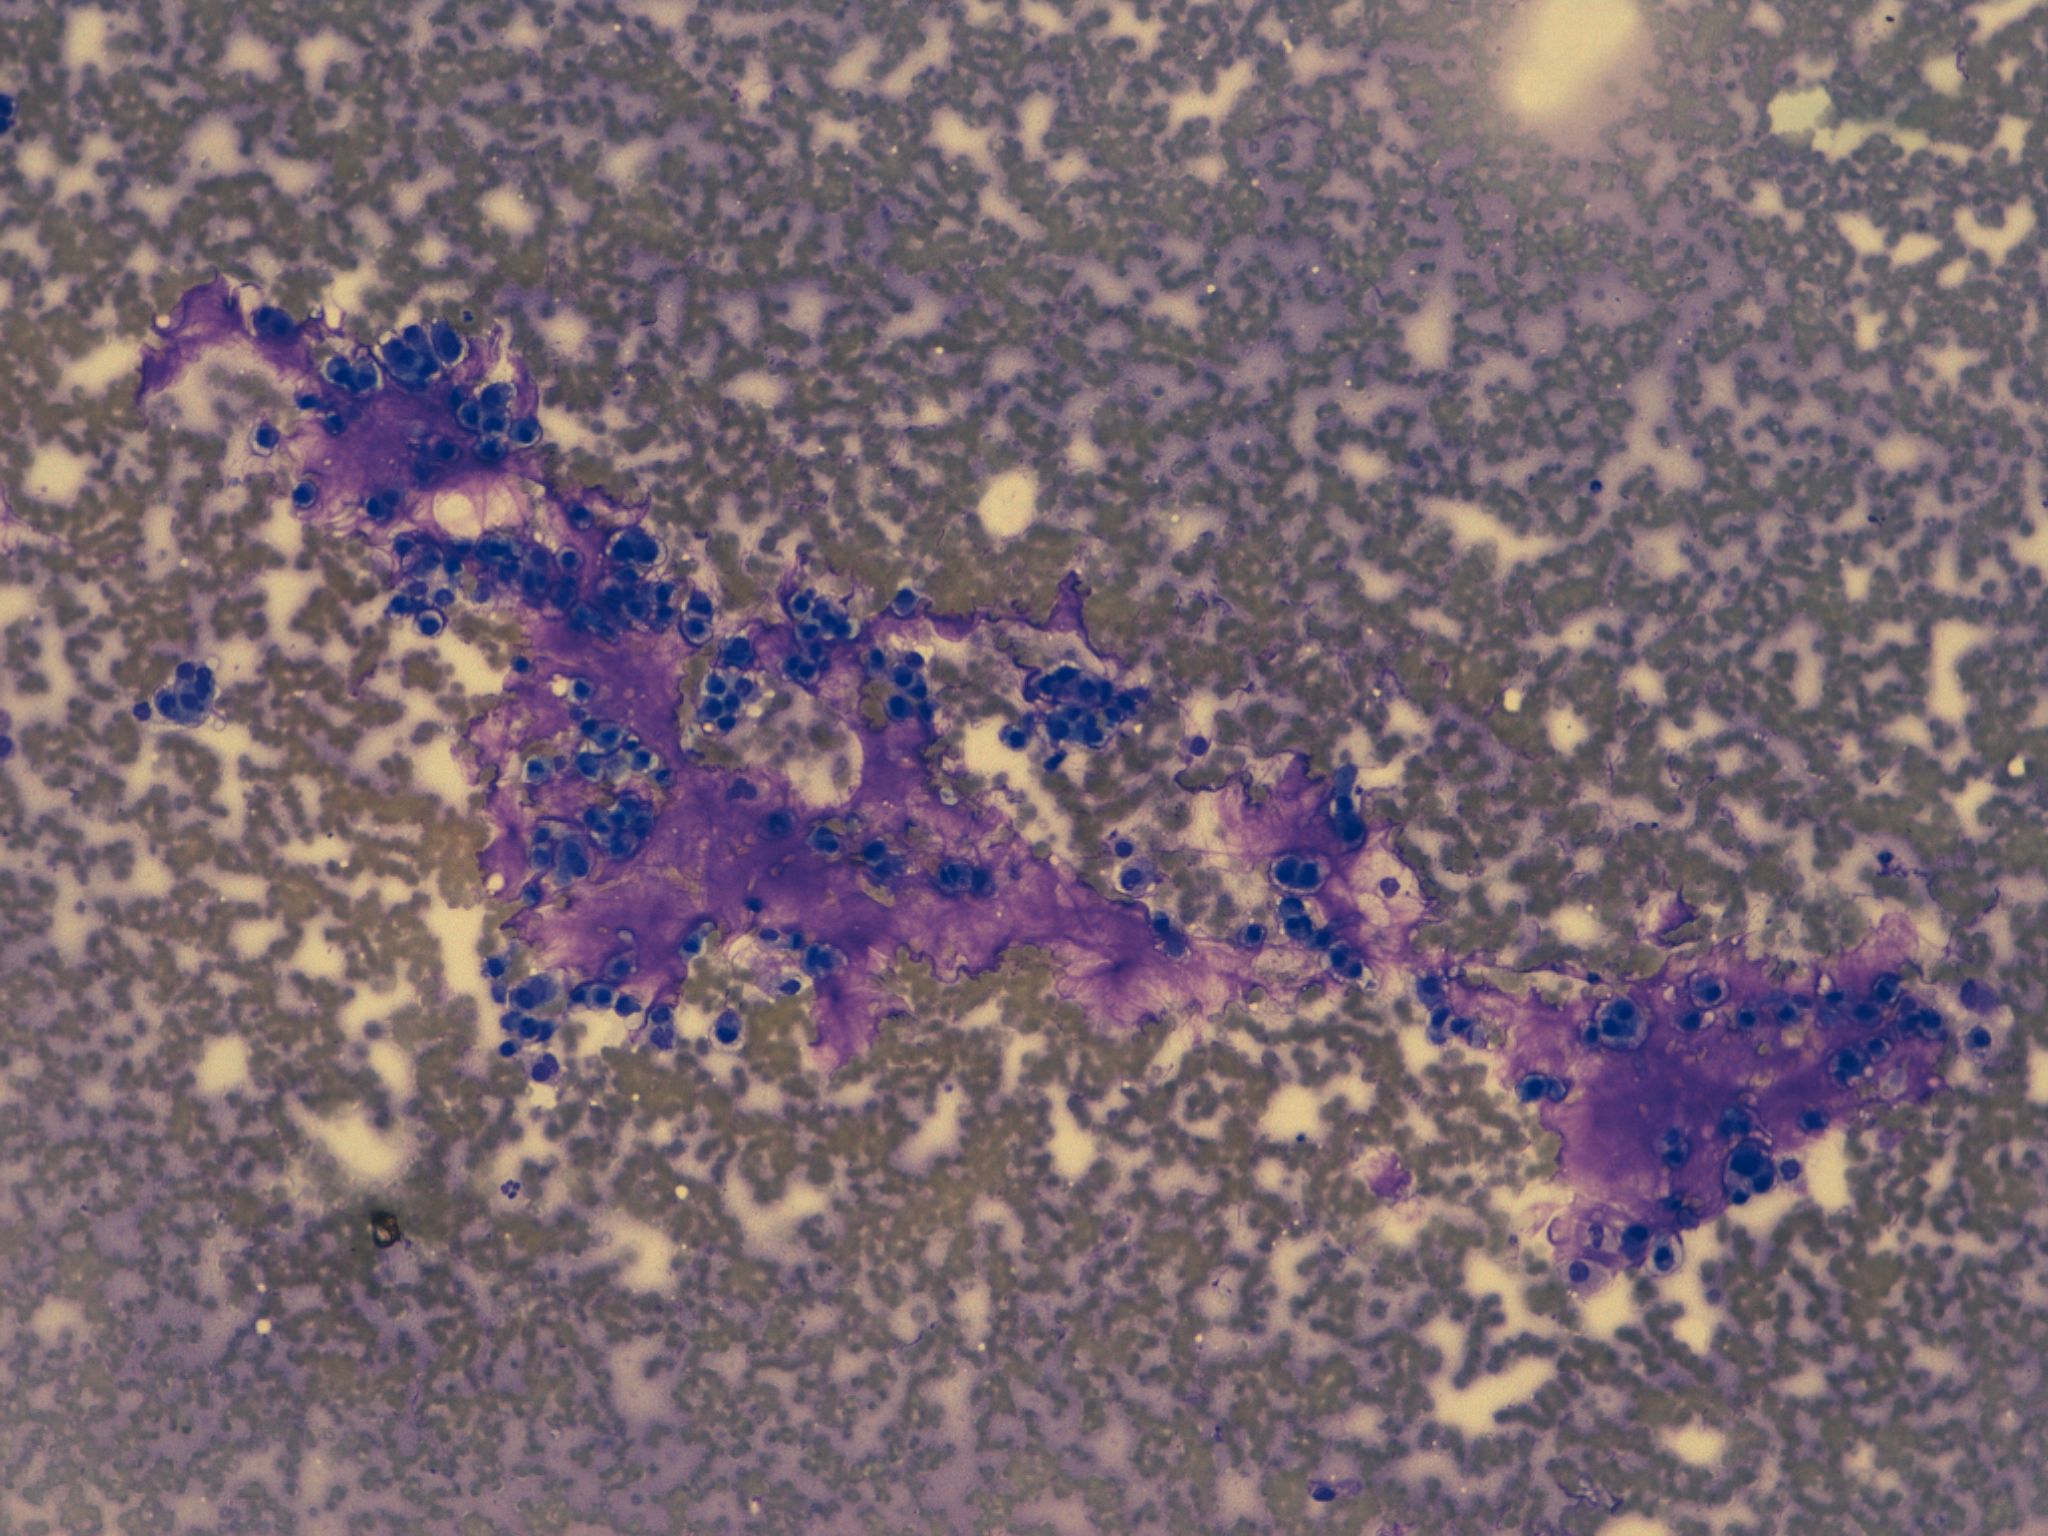

Dr. Ignacio Guasch, Dr. Edwin Mejía.

Hospital Germans Trias i Pujol, Badalona.

Hombre de 59 años, bronquítico crónico que refiere aumento del volumen mamario bilateral. Con una TC que informa masa tumoral en mediastino medio, voluminosa, sólido- quística, con extensa necrosis tumoral y adenopatías mediastínicas paratraqueales de tamaño significativo. Se realizar una PAAF guiada Ultrasonografía Ecobroncoscópica (EBUS) para el diagnóstico definitivo.